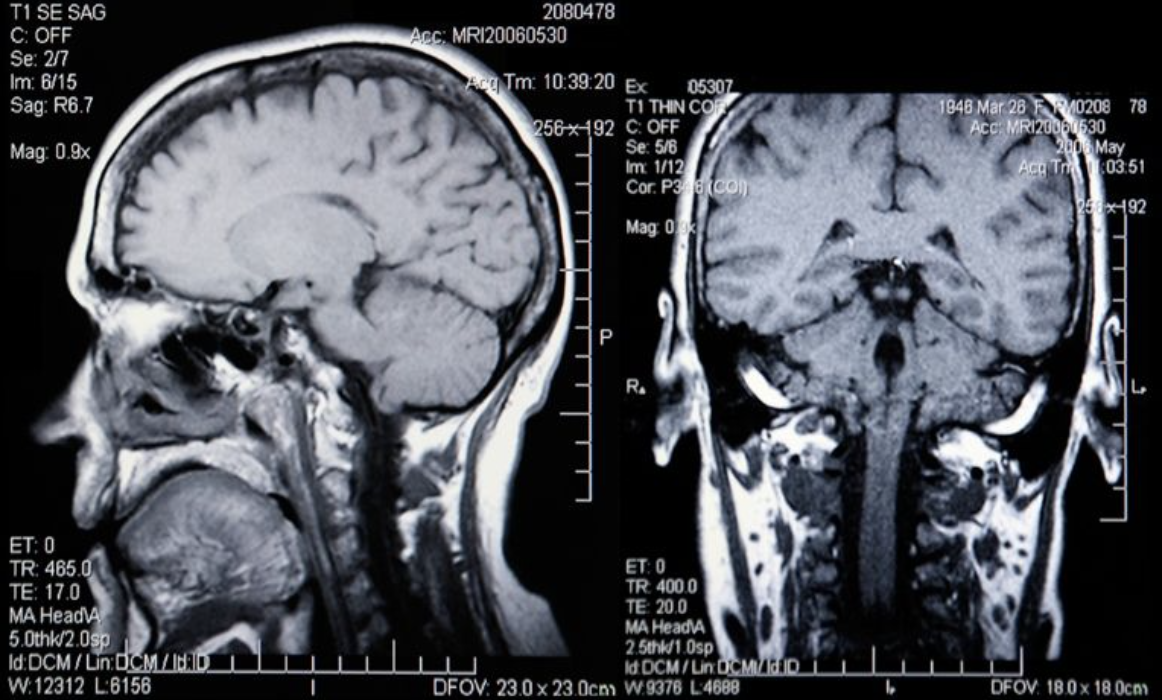

Иранские и американские авторы под руководством д-ра F.Rafiee опубликовали обзорную статью об изменениях в головном мозге пациентов с расстройствами аутистического спектра (РАС), выявляемых при магнитно-резонансной томографии (МРТ).

Авторы проанализировали существующие научные данные по теме и описали наиболее достоверные структурные, функциональные и молекулярные «признаки», могущие указывать на РАС по результатам визуализирующих исследований центральной нервной системы.